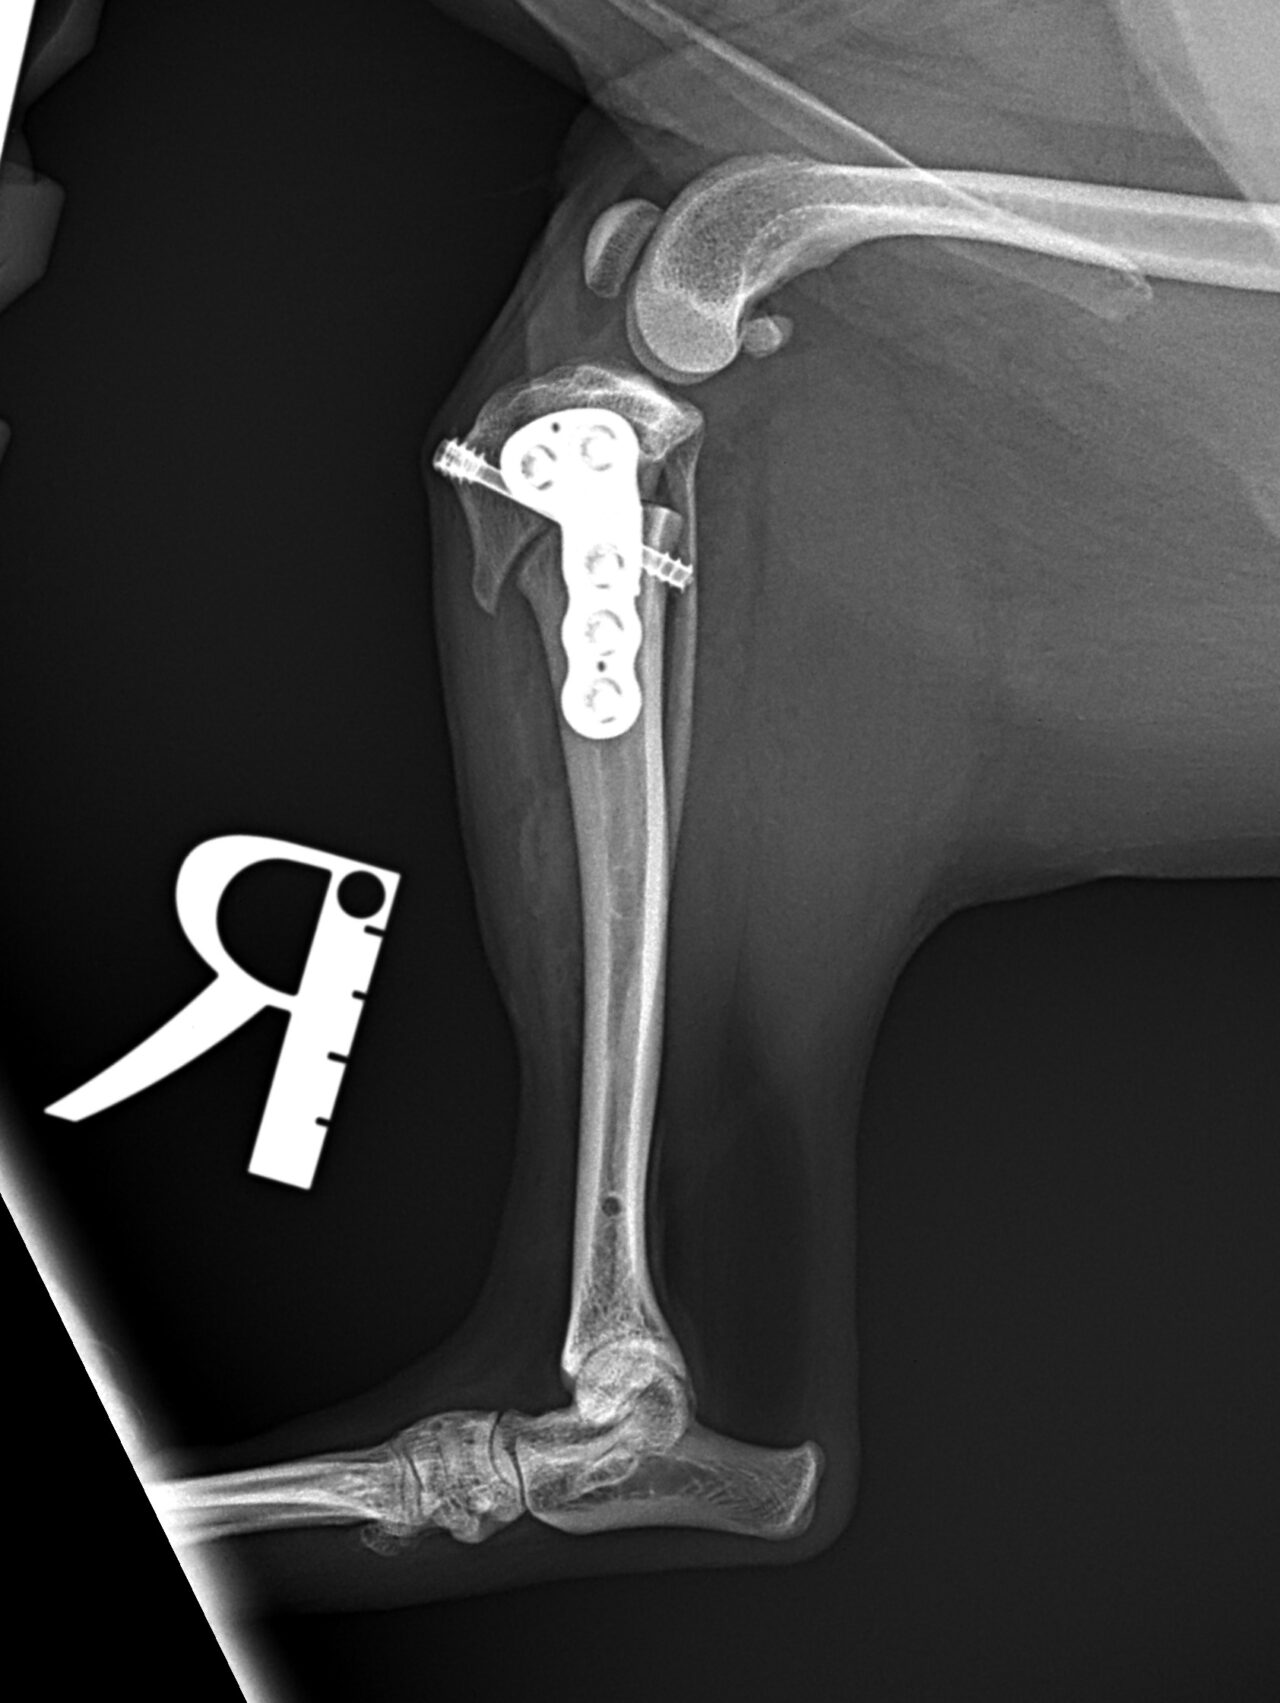

前十字靭帯断裂に対するCBLO #234 チワワの前十字靭帯断裂にCBLOで対応しました。骨切り部位の安定化にHCSとCBLOプレートを使用しています。しばらくは安静が必要です。 症例カテゴリー 放射線治療整形外科軟部組織外科脳神経外科内科腫瘍外科救急・集中治療リハビリテーション科腫瘍内科内視鏡科脳神経科呼吸器外科中医・漢方猫の腎移植循環器科